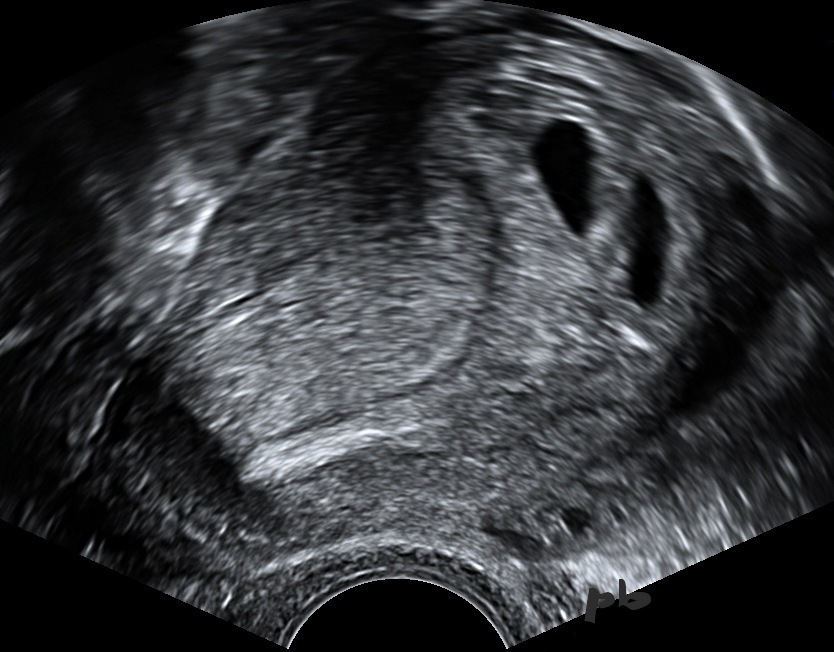

27 – EP + Dichorionic diamniotic IUP

Spontaneous triplet pregnancy. No ovarian stimulation.

Presence of 2 intrauterine gestational sacs.